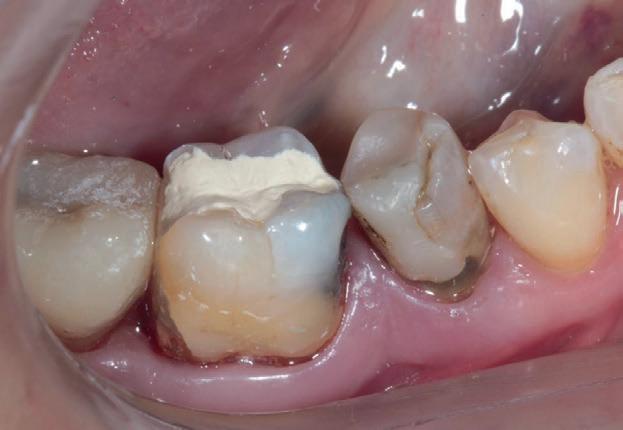

izolarea cu digă de cauciuc, restaurarea din amalgam a fost îndepărtată complet și s-a obținut accesul la cavitatea carioasă (fig. 3-5). În ciuda proximității față de țesutul pulpar, nu a avut loc nicio expunere, iar cavitatea de clasa a II-a a fost restaurată complet cu Biodentine™ (fig. 6-8).

Figurile:

6. Biodentine™ aplicat prin procedura

Bio Bulk-Fill. 7. Situația clinică după 12 minute și îndepărtarea matricii.

8. Situația clinică după îndepărtarea digii de cauciuc. 9. Radiografia de control la 2 luni postoperator.